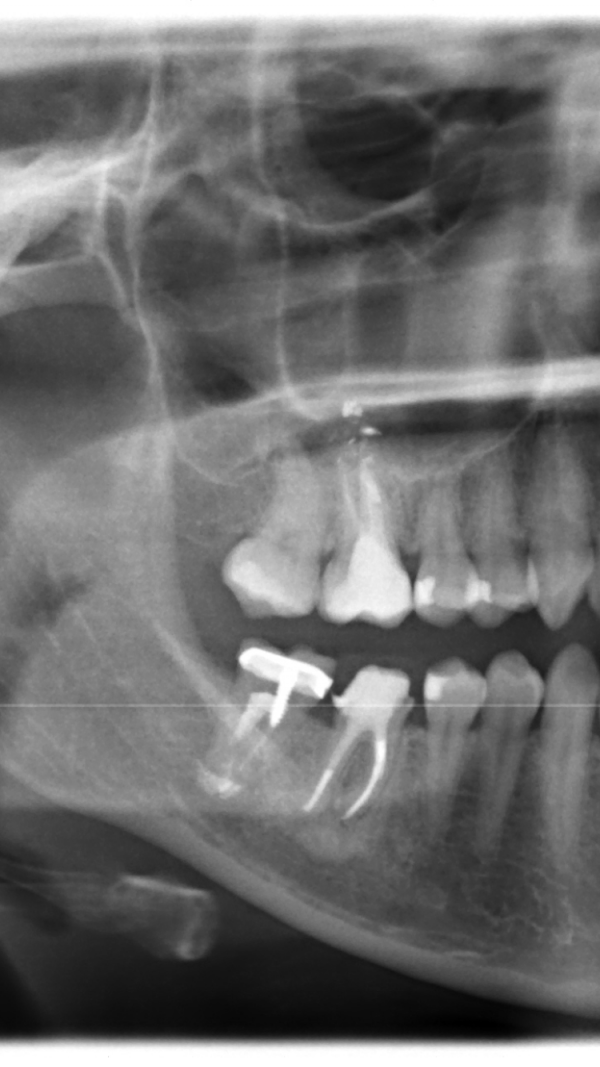

Имеется 7-й нижний зуб справа. Каналы пролечены 25 лет назад, возможно, резорциновым методом, и никогда не перелечивались. На зубе стояла сначала металлическая коронка, затем металлокерамика и керамика. Пару дней назад зуб отломился вместе с коронкой и штифтом под самый корень.

По данным снимкам, в периапикальной области (в области верхушки корня зуба) имеется скопление пломбировочного материала. Удивительно, что данный зуб прослужил 25 лет. Скорее всего, данный зуб запломбирован резорцин формалиновой пастой. После такого метода лечения каналов перелечивание каналов невозможно.

Если врачу удастся распломбировать канал для установки штифтовой конструкции, то, возможно, стоит согласиться на культевую штифтовую вкладку и коронку. Тем более, если зуб не беспокоит болезненными ощущениями.